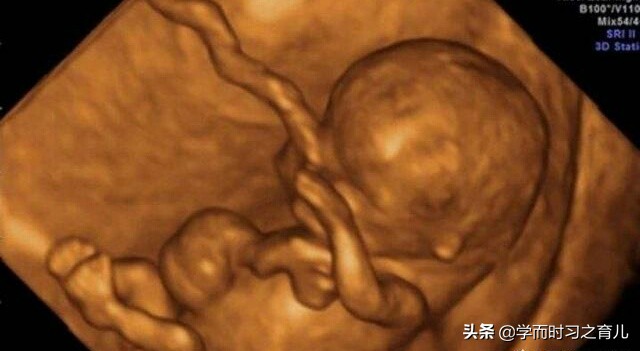

一般做四维彩超胎儿总是不露脸可能是由于宝宝正在揉眼睛、或者习惯性用手捂脸、再或者就是胎宝宝的体位挡住了脸等等。

如果做四维彩超一直看不到宝宝的脸就无法排除胎儿面部的畸形(比如唇裂等等),当然了,大部分胎儿的面部很少存在畸形情况,有时为了使孕妈咪更放心,也为了使检查更全面,医生一般会确保看到胎儿的脸,才算产检结束。

终于在第三次检查过后,表妹开心得出来了,对我说顺利过关。之后我问表妹医生怎么说的,表妹说:“医生说让我不要太担心,做四维彩超经常会遇到这种情况,一般多检查几次就可以看到胎宝宝的脸了,当然,这并不代表胎宝宝的发育出现了问题,另外,之所以一定要看到胎宝宝的脸,除了排畸,也有拍照的原因,这样可以让孕妇和家人看看胎宝宝的样子。”